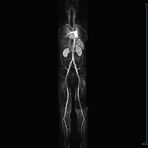

Ganzkörper Angiographie mit Kontrastmittel

• MR-Angiographie mit Kontrastmittel

• Erfassung arterieller und venöser Gefäße/Bypässe aller Körperregionen mit 3D-Rekonstruktion

• je nach klinischer Fragestellung zeitaufgelöste MR-Angiographie (4D-MRA) z.B. bei Frage arteriovenöse Fistel/ Shunt oder Darstellung Unterschenkelarterien vor geplanter Bypassoperation.